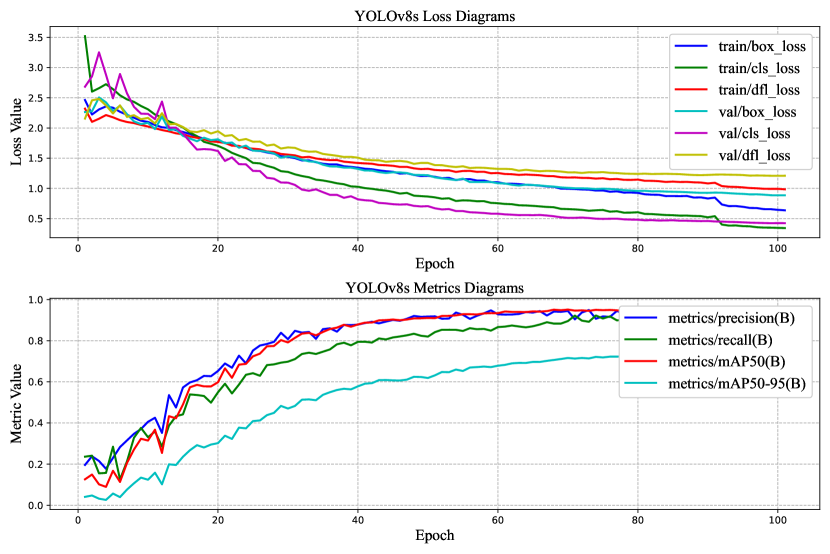

For the cervical vertebrae fracture detection, the models are trained 100 epochs and the results are demonstrated in Table 3.

mAP50 is the Mean Average Precision (mAP) at an IoU threshold of 0.5. IoU (Intersection over Union) is a metric used to measure the overlap between a predicted bounding box and a ground truth bounding box. A higher IoU threshold means that the predicted bounding box must overlap more with the ground truth bounding box to be considered a true detection. mAP50-95 is the Mean Average Precision (mAP) at IoU thresholds from 0.5 to 0.95. This is a more comprehensive metric than mAP50, as it takes into account the model’s performance at a wider range of IoU thresholds. Equations 4, 5, 6, and 7 define the formulas for mAP50, mAP50-95, Recall, and Precision.

For fracture detection based on the results, it is clear that the performance of YOLOv8 outperforms YOLOv5. This is a significant improvement, especially considering that YOLOv8 is also faster than YOLOv5. Furthermore, although YOLOv8m has more parameters the mAP50 for YOLOV8s is a bit higher. On the other hand, YOLOv8m has higher mAP50-95. It is evident that YOLOv8s has demonstrated a strong ability to correctly classify images as “Normal" with 194 true positives and only 6 false negatives as presented in Figure 9.